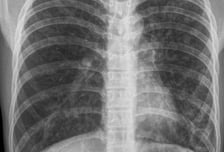

"폐암 검사 아냐?" 오히려 조기 발견 방해…환자단체 목소리 내는 이유

폐암 환자단체가 흉부 X선 검사로는 암을 조기 발견할 수 없다며 인공지능(AI) 진단 보조 시스템의 도입, 저선량 흉부 CT 검사 대상 확대 등을 국회에 공식 요청했다. 오히려 흉부 X선 검사를 받았다고 안심하는 것이 폐암 진단을 방해할 수 있다고 했다. 실제 보건복지부는 환자단체 등의 주장을 수용해 올해부터 국가건강검진 결과지에 "흉부 X선은 폐암 선별 검사가 아니다"는 문구를 삽입했다. 하지만 이런 사실을 모르는 사람이 의외로 많다. 한국폐암환우회는 전날 국회 보건복지위원회 소속 더불어민주당 김윤 의원에게 폐암 검진 사각지대 해소를 위한 정책 제안서를 전달했다고 21일 밝혔다. 이 자리에서 조정일 폐암환우회장은 "현재 2년마다 진행되는 건강검진에 포함된 흉부 X선만으로는 폐암을 조기에 발견할 수 없다"고 지적했다. 이어 "오히려 흉부 X선 검사로 폐암 발견이 가능할 것이라는 오해가 조기 진단을 막는다"며 △흉부 X선 검사에 AI 판독 보조 시스템의 도입과 접목 △흡연력 외에 폐